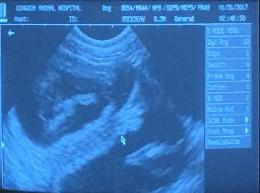

On January 30th I will have an USG done to confirm the pregnancy

January 30, 2016   We have a confirmed pregnancy       puppies due around March 2nd.